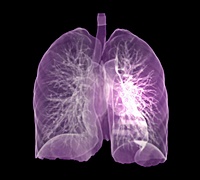

4. CT 스캔

CT 스캔은 폐 손상의 정도를 평가하는 데 유용한 검사입니다. 특히 폐포 파괴가 특징인 폐기종을 감지하는 데 유용합니다. CT 스캔은 폐 손상의 위치와 정도를 정확히 파악하여 치료 결정을 도울 수 있습니다.